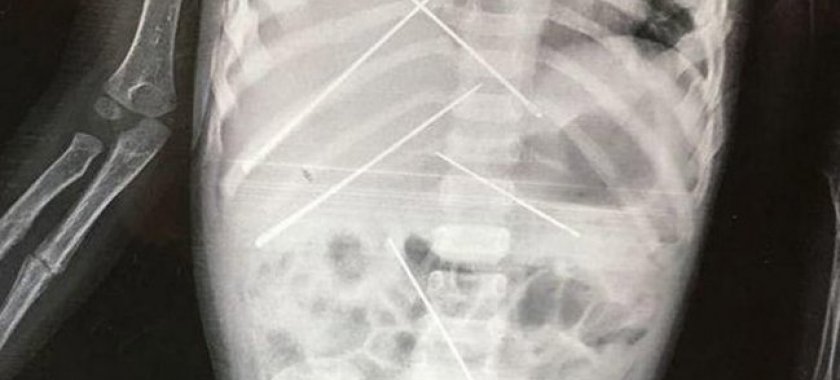

Renten kağızında qızın bədəninə batırılan 7 ədəd iynənin olması əks olunub. İynələrin birinin uzunluğu təxminən 4 santimetrdir.

Qız ötən gün əməliyyat edilib. Həkimlər onu travmadan çıxarmağa çalışırlar.

Həkimlərin qızın anasının dediklərinə əsasən söylədiklərinə görə, iynələr 15-20 gündən artıqdır ki qızın bədənindədir.